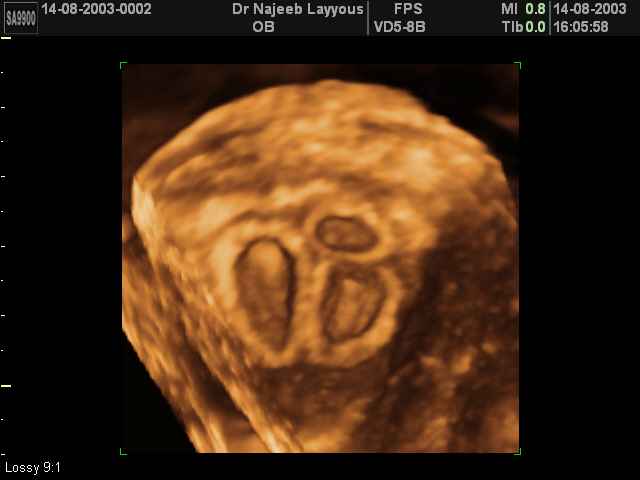

- صور لتوائم

صور لتوائم بجهاز الالتراساوند ثلاثي الأبعاد | الدكتور نجيب ليوس